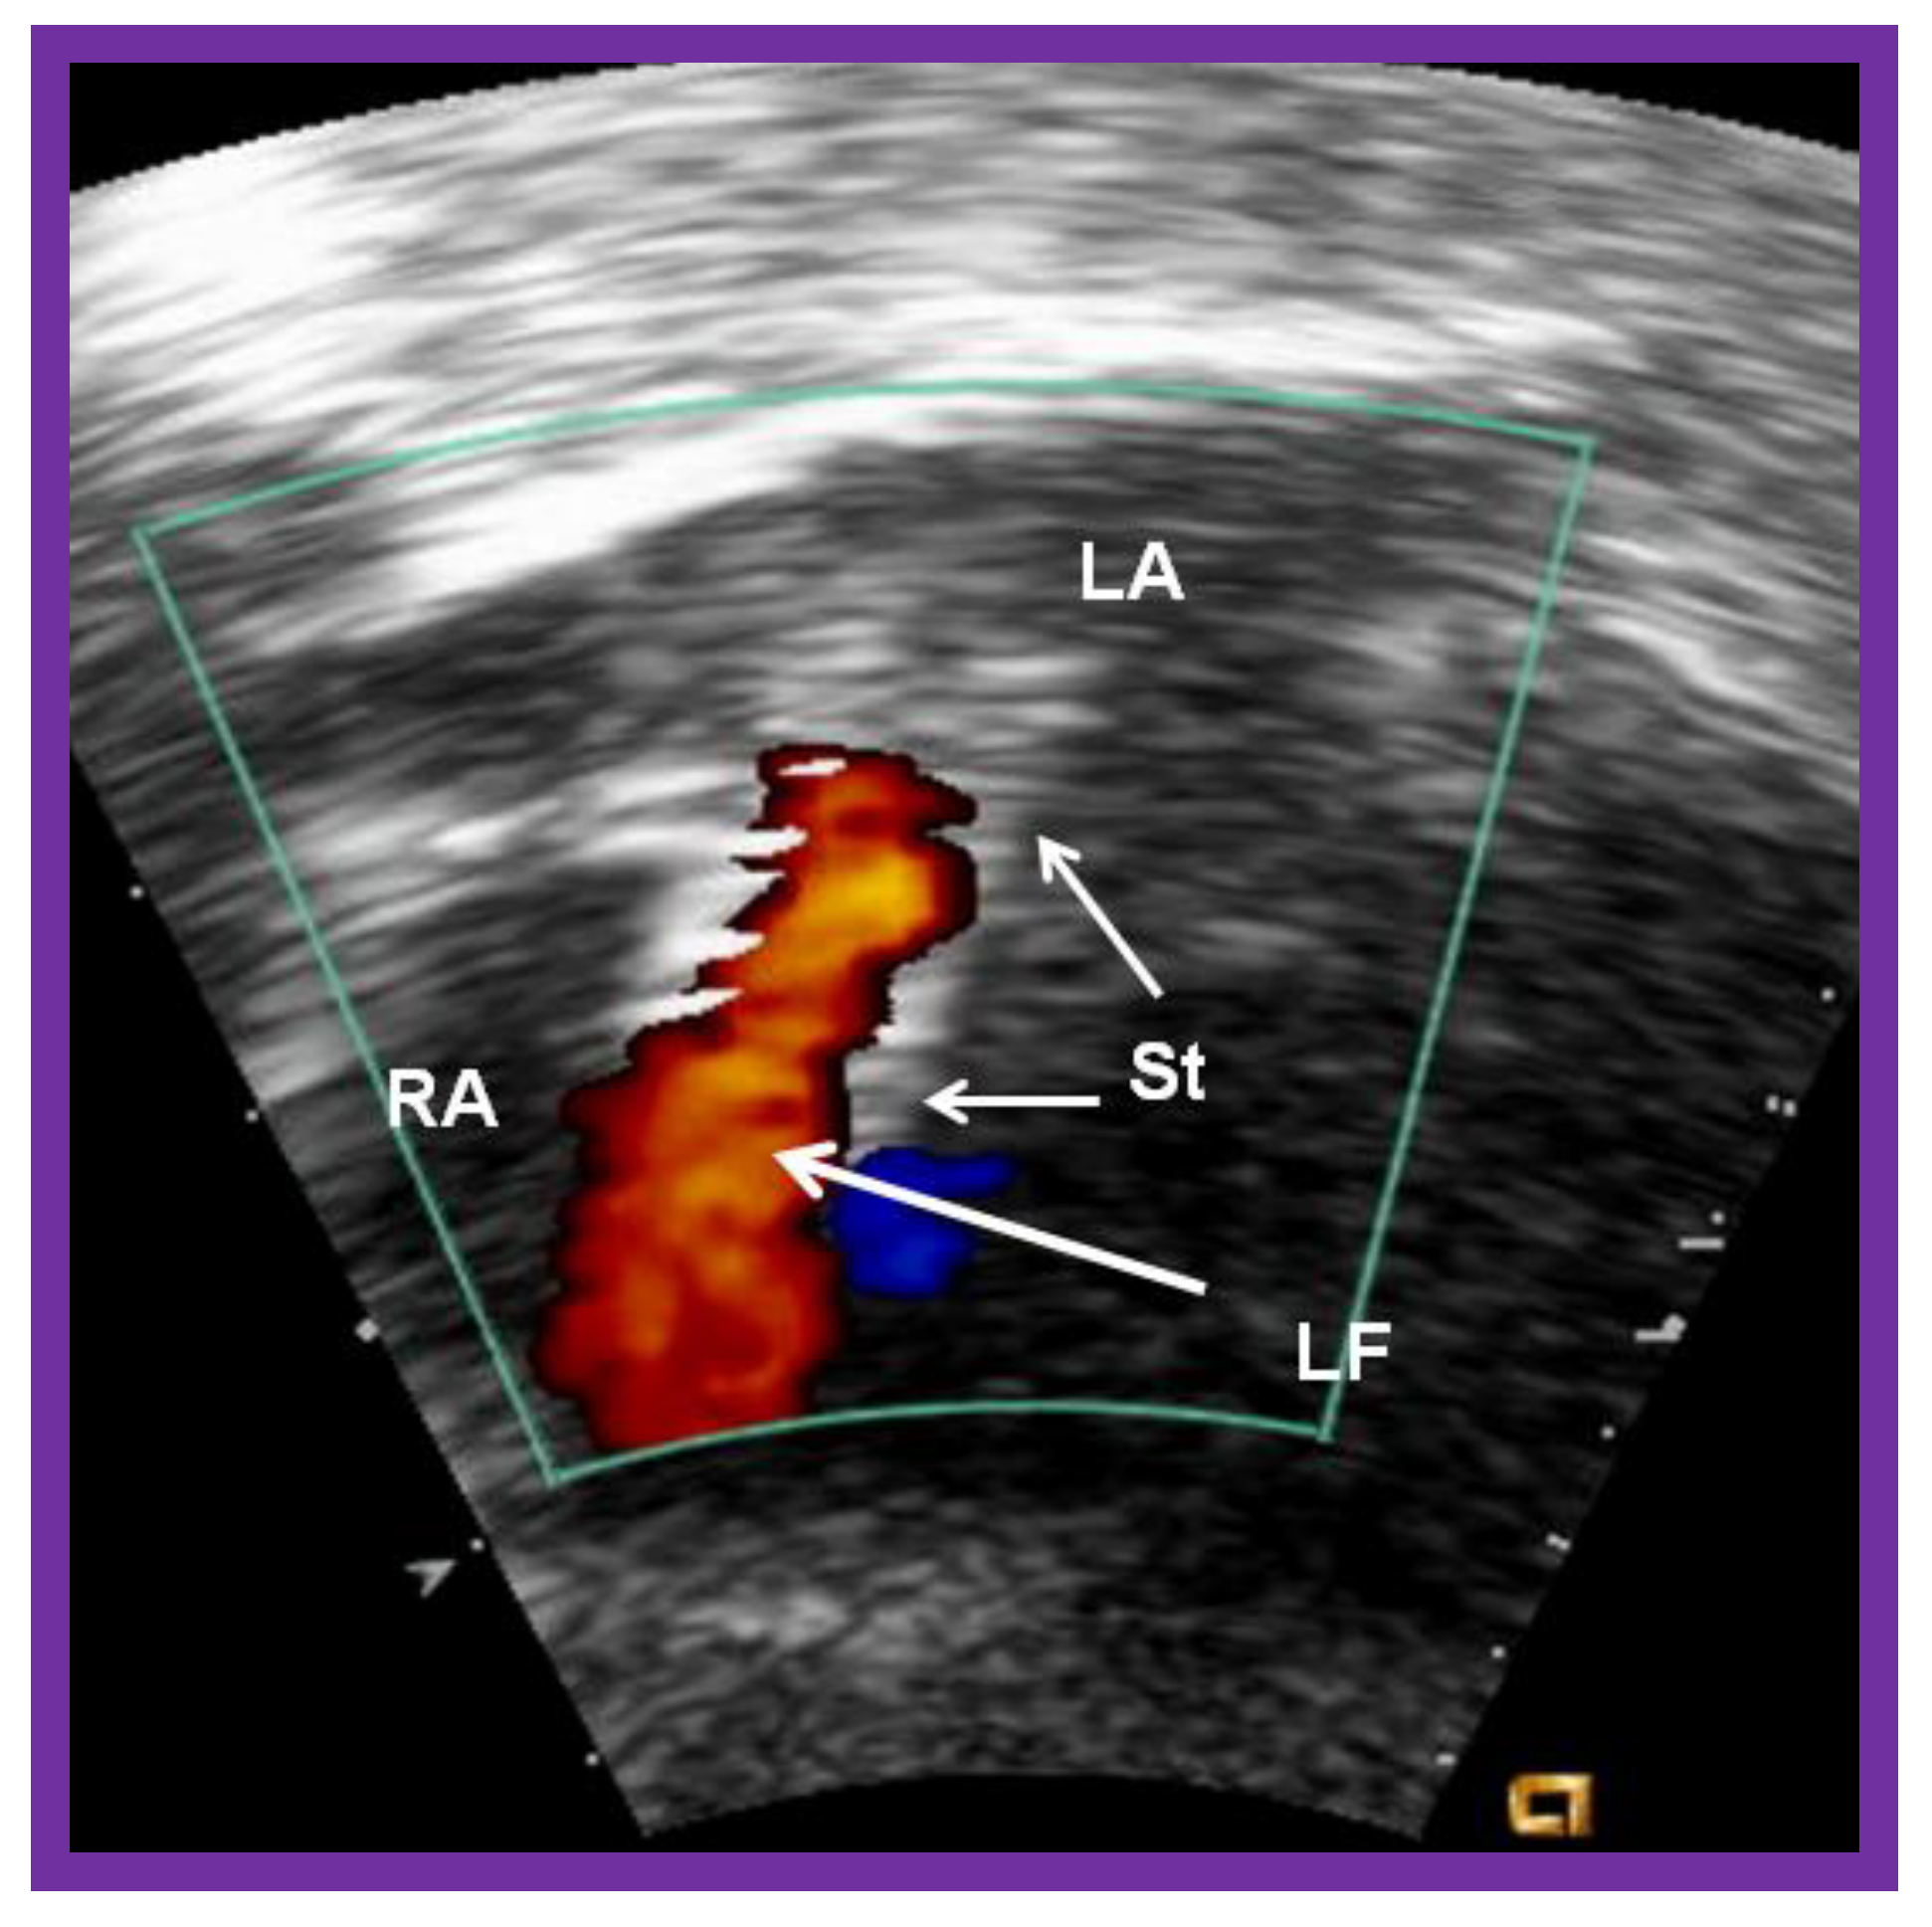

5.1. Restrictive Atrial Communication

Figure 19.

Selected cine (A) and video (B) frames demonstrating the location of the stent (St) across the atrial septum following St deployment. LA, left atrium; RA, right atrium; PG, pigtail catheter in the descending aorta. Reproduced from Reference [89].

Figure 20.

Video frame of the stent (St) (short arrows) demonstrates laminar flow (LF) (long arrow) across it. LA, left atrium; RA, right atrium. Reproduced from Reference [89].